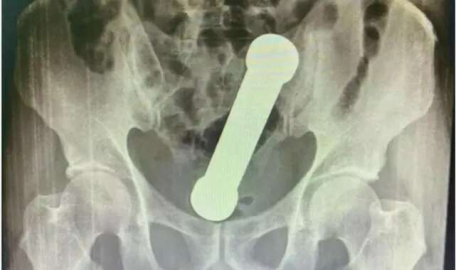

Brezilya’da yaşanan inanılması zor olayda; doktorlar, kramp ve şiddetli kabızlık şikâyeti ile acile giden 54 yaşındaki adamın röntgen filmi çıktığında gözlerine inanamadı. Röntgen filminin sonucuna göre 54 yaşındaki adamın rektumunda iki kiloluk bir dambıl vardı.

Muayene esnasında belli olmayan durum, hastanın röntgen filmi çekilince ortaya çıktı. Brezilya’nın Manaus kentinde yaşanan olayda sağlık görevlileri, cımbız kullanarak nesneyi dışarı çıkarmaya çalıştılar ancak başarısız oldular. Sonrasında daha acımasız bir yönteme başvurdular ve elle çıkarmayı denediler. BAŞARIYLA ÇIKARILDI

International Journal of Surgery Case Reports’da yer alan olayda cerrahi ekip raporuna şunları yazdı: "Nesne, kalıcı bir komplikasyon beklenmeksizin başarıyla çıkarıldı"